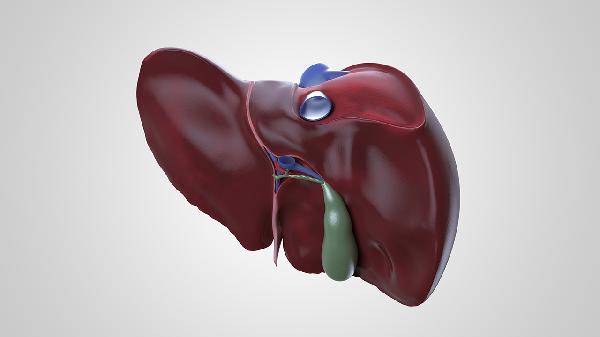

肝臟鈣化灶是肝臟組織中的鈣鹽沉積現(xiàn)象,通常由既往炎癥愈合、寄生蟲感染、血管瘤鈣化、膽管結(jié)石或代謝異常等因素引起。